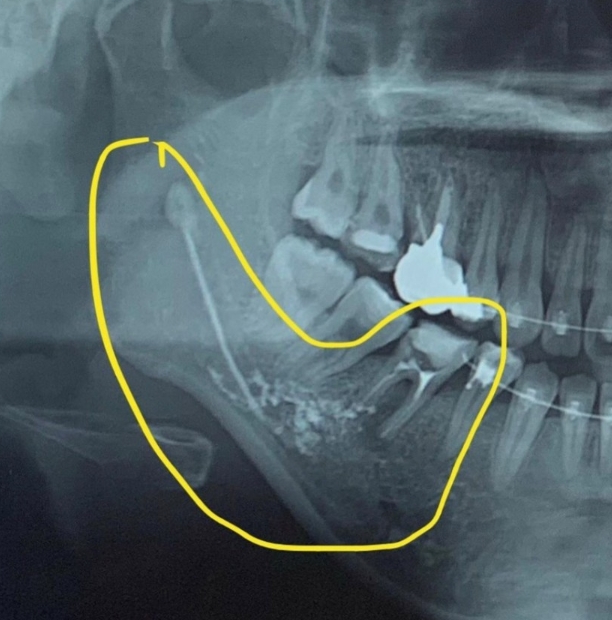

해당 치과에서 치료를 받은 시민 A 씨는 최근 자신의 SNS에 “강남 유명 모치과에서 신경 치료 중 약물이 신경관으로 넘어가 하치조신경 마비, 영구장애로 살아가야 할 처지다”라는 글을 게재했다.

A 씨는 “삼차 신경 손상 진단받고 계속 약물치료 중이다. 수술하게 되면 양악수술처럼 턱뼈를 열어서 해야하나 후유증이 너무 크고, 나중에 되면 신경차단술로 통증을 완화시키기 위해 신경을 아예 없애야 한다고 한다”고 밝혔다.

하지만 신경관에 들어간 약물이 수용성이고, 매우 얇은 관을 타고 올라간 상태라 가능성이 희박한 상태.